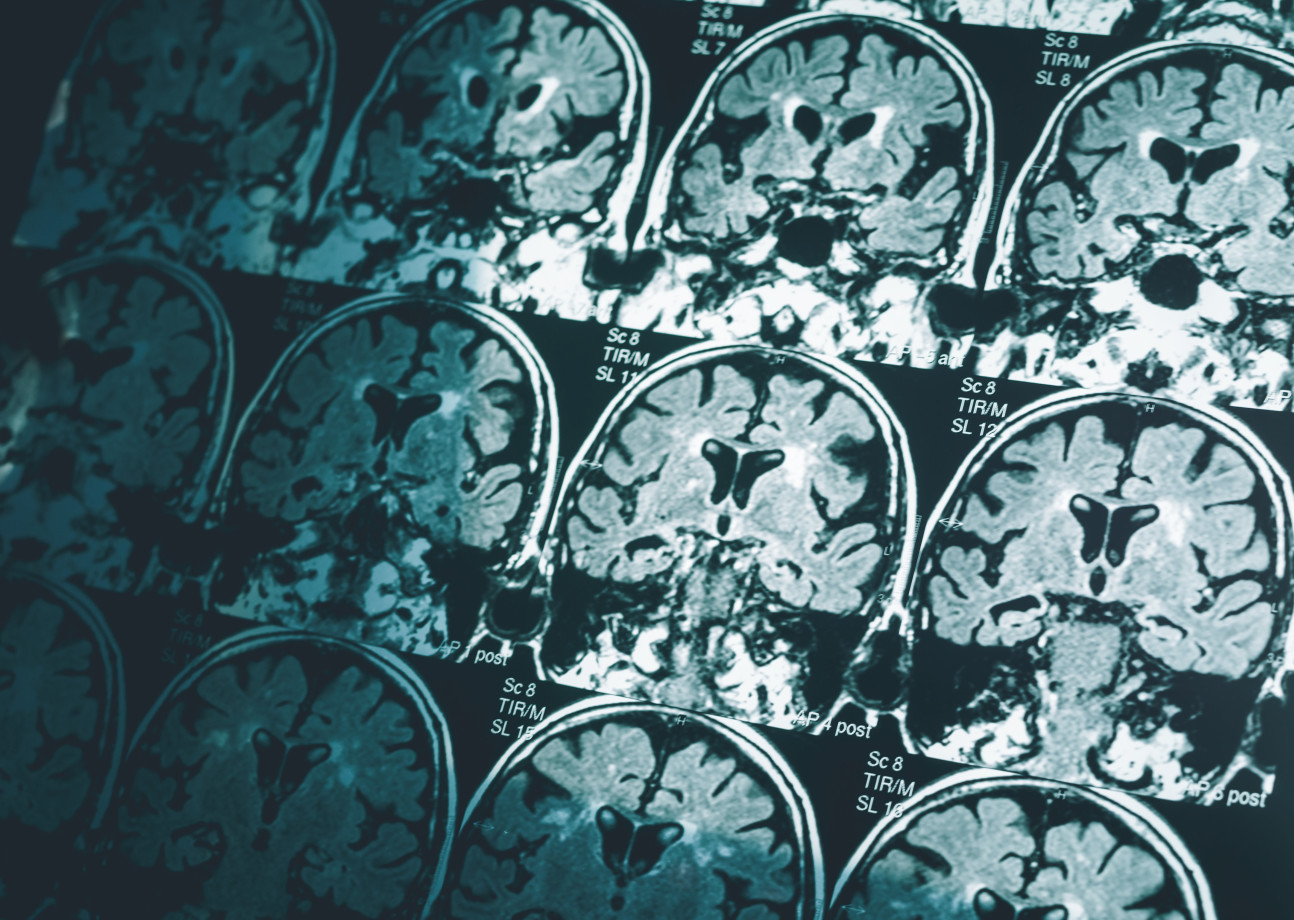

Machine learning technology detects Alzheimer’s with just one brain scan

A series of MRI brain scansUsing machine learning technology, researchers at Imperial were able to successfully predict the presence of Alzheimer’s disease in 98% of cases with a single MRI scan of the brain.

This technology, announced in June, would allow for the detection of Alzheimer’s at very early stages of the disease, which is currently quite difficult to do. Having an early diagnosis would give patients time to plan and receive the support that they need well in advance of disease progression.

Lead author Professor Eric Aboagye from Imperial’s Department of Surgery and Cancer explained: “Waiting for a diagnosis can be horrible for patients and their families. Currently no other simple and widely available methods can predict Alzheimer’s disease with this level of accuracy, so our research is an important step forward.”